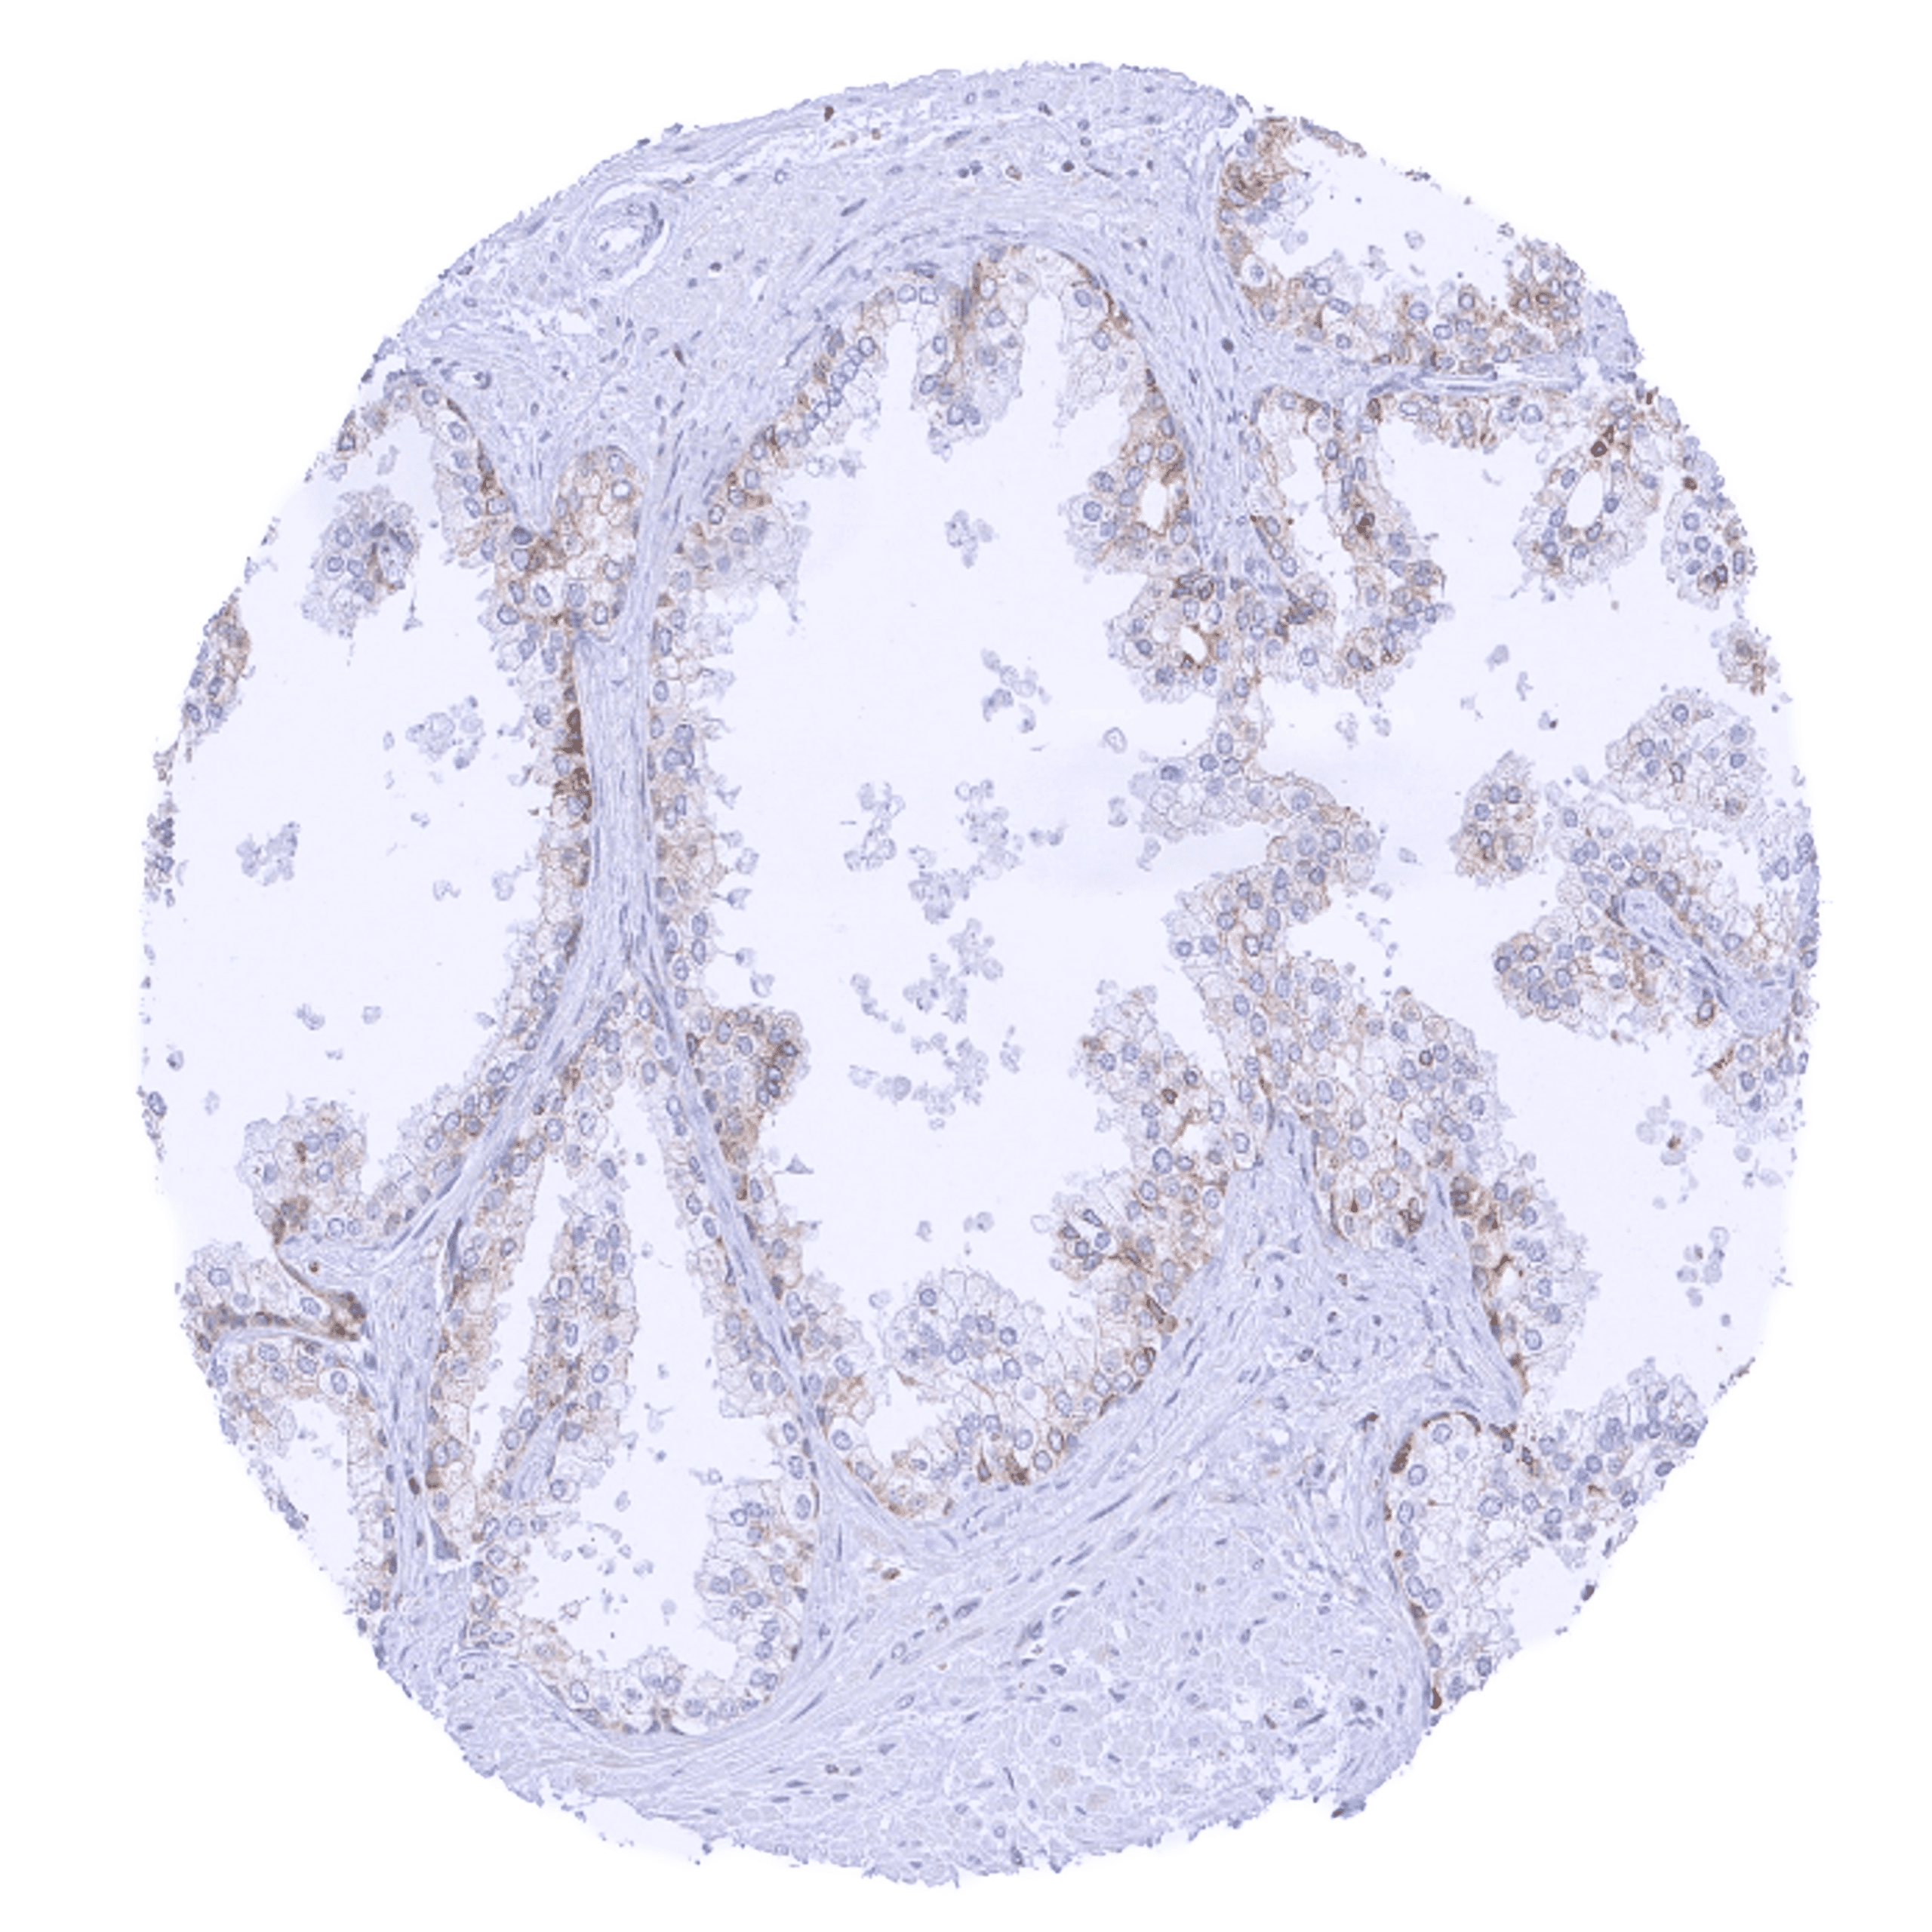

| Female genital | Breast | Distinct cytoplasmic bcl-2 staining of epithelial cells (acinar cells stain stronger than myoepithelial cells). |

Bcl-2 expression of variable intensity can occur in all types of cancer. It is particularly common in follicular lymphoma.

Comparison of antibodies: True expression of bcl-2 in all cell types with documented bcl-2 immunostaining by MSVA-402M is validated by identical staining patterns obtained by a second, independent commercially available bcl-2 antibody, termed “validation antibody” for all analyzed tissues.